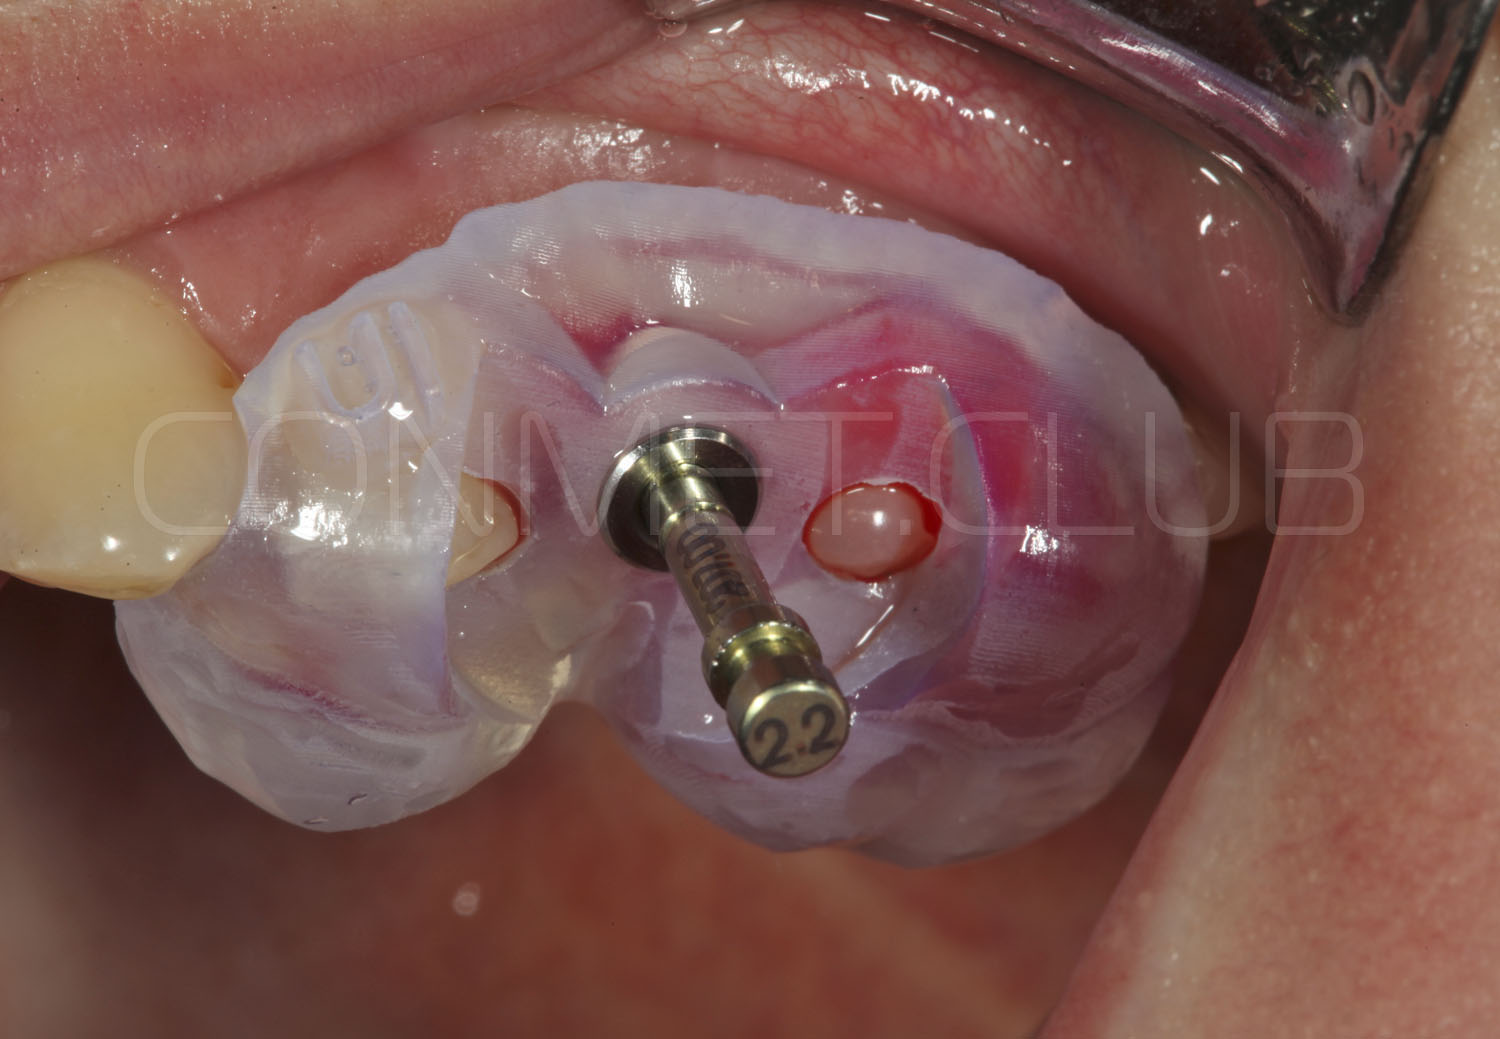

Направляющие втулки нового типа имеют цветовую маркировку (с диаметром отверстия 2,2 мм - серебристого цвета и 2,8 мм - золотистого цвета), а также одинаковый внешний диаметр, что позволяет использовать 2 одинаковых шаблона, но с втулками разного диаметра.

Характерной особенностью новых втулок является их фиксация в шаблон без использования клеев или адгезивов. Это значительно упрощает работу при фиксации втулок в шаблон и абсолютно исключает попадание фиксирующего клея внутрь втулок.

Имплантат устанавливается в подготовленное ложе. Так как не производится широкого откидывания слизисто надкостничных лоскутов и операция проводится через маленькое перфорационное отверстие, кровоточивость и сама операционная травма - минимальные.